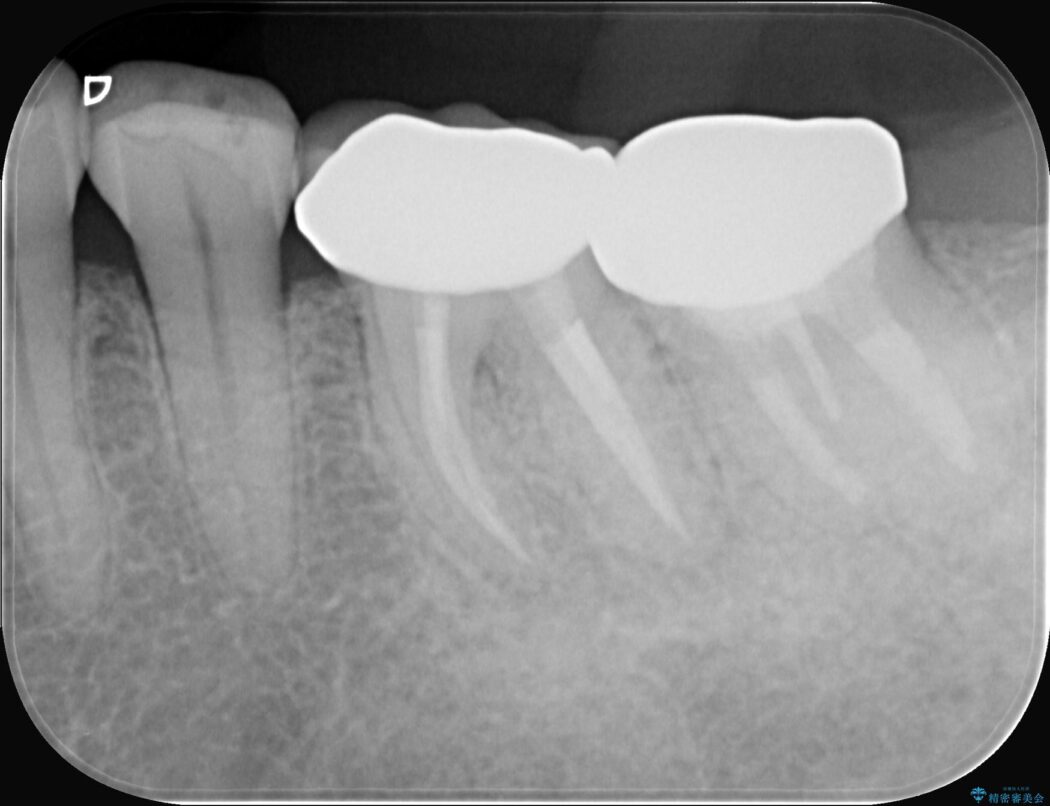

レントゲンを確認すると、歯髄腔が狭くなり根管が石灰化している難症例でした。

患者様の大切な歯を残すため、歯科用顕微鏡を用いた精密根管治療を行うことで、狭く、見えにくい根管を正確に探し出し、治療を完了させる計画を立案しました。

今回の治療は、特に難易度の高い石灰化した根管が対象でした。

まず、治療中の細菌感染を防ぐためにラバーダムを使用。次に、歯科用顕微鏡で治療部位を何十倍にも拡大しながら、狭窄した根管の入り口を探し、慎重に拡大・清掃を行いました。顕微鏡を用いることで、肉眼では不可能だった根管内部の細かい構造を確認しながら、感染源を徹底的に除去することができました。これにより、難症例の奥歯でも再発リスクを抑えた適切な処置を行うことができ、治療後に痛みは解消。大切な歯を長期間にわたり保存することができました。